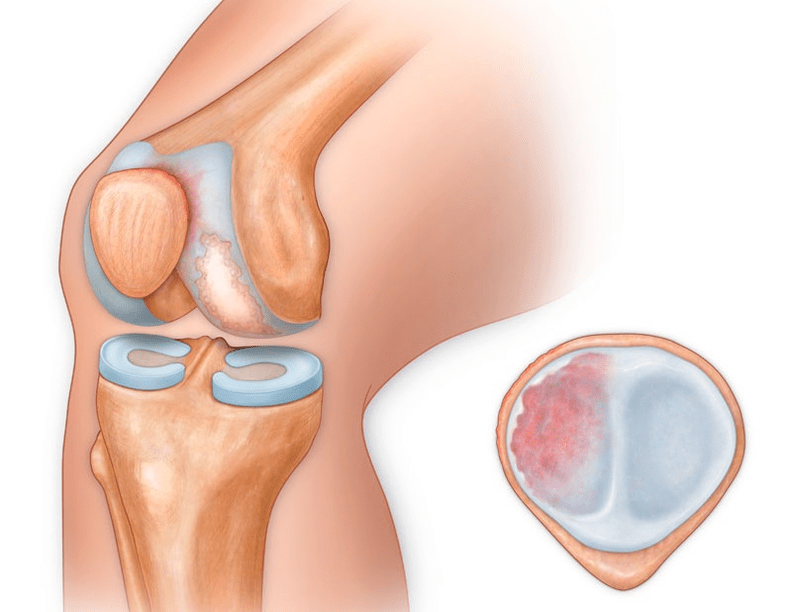

In addition to the inner or outer part of the knee, osteoarthritis can also affect the surfaces between the patella and the intercondylar groove of the femur.This option is calledpatellofemoral osteoarthritis.

Its cause is generally a subluxation, fracture or lateralization of the patella.

With osteoarthritis (osteoarthritis), in addition to the gradual destruction of cartilage, loss of its elasticity and cushioning properties, bones are gradually involved in the process.Under load, sharp edges (exostoses) appear, which are incorrectly considered "salt deposits" - with classic osteoarthritis, no salt deposits occur.As osteoarthritis progresses, it continues to “eat” the cartilage.Then the bone deforms, cysts form on it, all structures of the joint are affected and the leg bends.

Until the mid-80s of the last century, there was no unified definition of the disease.It was not until 1995 that the Osteoarthritis Committee of the American College of Rheumatology characterized the disease as the result of mechanical and biological factors leading to an imbalance between the processes of degradation and synthesis of the extracellular matrix of articular cartilage.As a result, disintegration and degeneration of fibers occurs, cracks, osteosclerosis and compaction of the cortical layer of the subchondral bone are formed, osteophytes develop and subchondral cysts are formed.